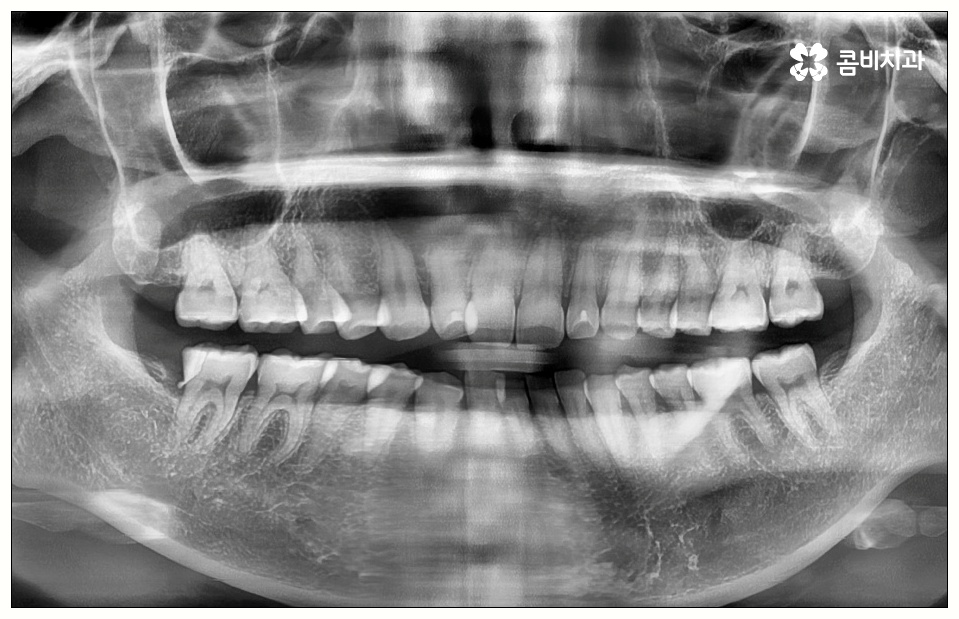

하지만 꼭 발치 처치를 받아야 하는 사랑니도 있는데 그 중 대표적인 것이 바로 어금니 사이 충치 를 유발한 경우로, 비스듬하게 나온 사랑니가 앞의 어금니를 밀면서 압박을 주고 옆면에 충치를 일으키는 등 손상시키고 있다면 늦기 전에 발치 처치를 받으실 필요가 있습니다.

이 때 어금니 뒤쪽으로 비스듬하게 사랑니가 자리를 잡으면 부분적으로 맹출이 되면서 치아 사이에 좁은 틈새가 만들어져 여러 가지 부산물들이 끼기 쉬워지는 반면 칫솔질 등 관리는 더욱 어려워지기 때문에 구강 질환 발생률이 높아질 수 있어요.

위생 관리가 제대로 되지 않으면 치태와 치석이 늘어나 세균이 증식하면서 구취는 물론 충치가 유발되게 되는데, 이것을 방치할 경우 사랑니 자체가 썩어 옆의 어금니로 충치가 옮겨가게 되거나 사랑니와 어금니 사이 충치 발생으로 인해 어금니까지 덧씌워야 하는 상황이 올 수도 있으니 주의하실 필요가 있어요.

특히 어금니 사이 충치 는 눈에 잘 보이지 않을 뿐만 아니라 어느 정도 진행이 될 때까지 통증이 크지 않기 때문에 치료시기를 놓치게 되는 경우가 많이 있는데요.

이렇게 병증이 깊어지게 되면 치은에도 쉽게 손상이 일어나고 치아 내부 밀도가 떨어져 치아 파절이 일어날 수 있으며 결국 사랑니만 뽑는 것이 아니라 저작 기능에 중요한 역할을 하는 어금니까지 발치해야 하는 상황이 생길 수도 있기 때문에 초기에 잘 대처하실 필요가 있어요.

치아 사이 충치는 법랑질이 두꺼운 교합면, 즉 음식을 잘게 부수는 윗면이 아니라 치아와 치아 사이에 맞닿고 있어 비교적 법랑질의 두께가 얇고 신경까지의 거리가 짧은 옆면에 생기는 것이기 때문에 병증이 진행되는 속도가 빠르고 치료하기가 까다로워 될 수 있는대로 빨리 대처하실 필요가 있어요.

사랑니로 인해 어금니 사이 충치 가 발생하고 치아 파절이 일어나 신경까지 손상이 일어난 경우 원인이 된 사랑니를 발치한 후에 신경 치료와 크라운 처치를 통해 어금니 수복을 해 주게 되는데 이 때 근관 소독 및 밀봉 후 통증이 없어졌다고 해서 크라운 처치를 해 주지 않은 채로 치료를 마치게 되면 2차 감염이 일어나거나 외부 충격으로 인해 또 다시 파절이 생길 가능성이 높아 어렵게 살린 어금니를 잃게 될 수도 있으니 꼭 남아 있는 치아를 전체적으로 덮어주는 크라운 처치를 통해서 보호해 주시는 것을 권유드리고 있습니다.